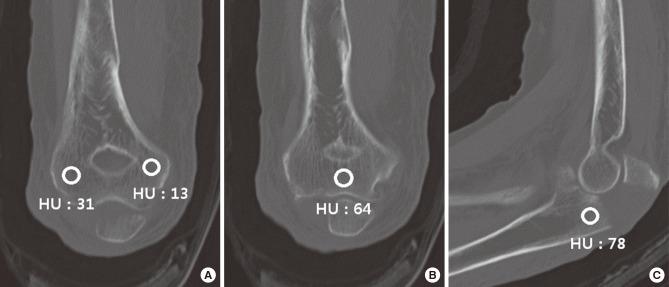

METHODS

Elbow computed tomography (CT) and medical record review were performed in 114 patients (53 males and 61 females) with acute olecranon fractures. The mean age was 57 years. Bone attenuation was measured on the central part of the olecranon on sagittal CT images avoiding the fracture, and on the distal humerus (distal metaphysis and medial and lateral condyles) on coronal CT images. We compared bone attenuation and causes of injury (high or low energy trauma) between younger (<50 years) and older (≥50 years) patients in each gender. Multiple regression analysis was performed to determine the effect of age and gender on bone attenuation.

对114例急性鹰嘴骨折患者(53例男性和61例女性)进行肘部计算机断层扫描(CT)及病历回顾。平均年龄为57岁。在矢状位CT图像上避开骨折部位测量鹰嘴中央部分的骨密度,并在冠状位CT图像上测量肱骨远端(远端干骺端以及内外侧髁)的骨密度。我们比较了不同性别中年轻(<50岁)和年长(≥50岁)患者之间的骨密度及损伤原因(高能量或低能量创伤)。进行多元回归分析以确定年龄和性别对骨密度的影响。